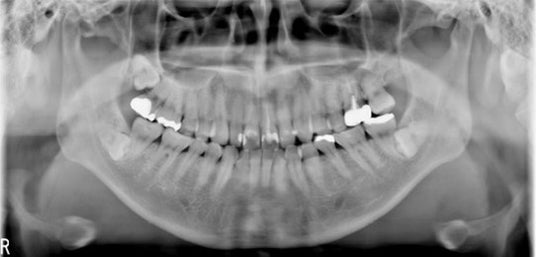

デンタル撮影に関しては、歯が最も明瞭に描出されている断面位置を自動的に作成するオートフォーカス機能を備えており、【図5】に示すように、短時間で全顎のデンタル撮影(10枚法や14枚法)のテンプレートを自動的に作成することができます。

【図5】:歯牙の軌道や傾きに合せた全顎のデンタル画像をオートフォーカス機能で自動的に出力できる機能(図は14枚法テンプレートの例)

歯軸にフォーカスの合った画像